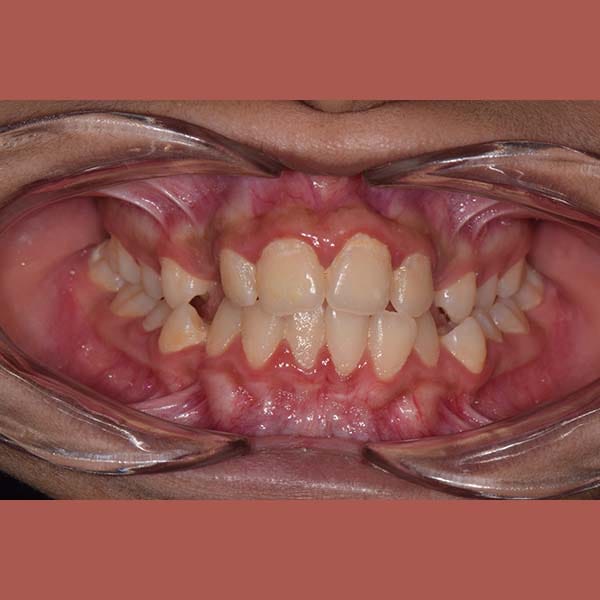

BEFORE

This girl suffered from severe upper jaw stenosis, which negatively affected her smile,

suppressed the beauty of her white teeth when smiling, and also led to a buried upper-right canine in the bone, and a reverse bite in the back teeth.